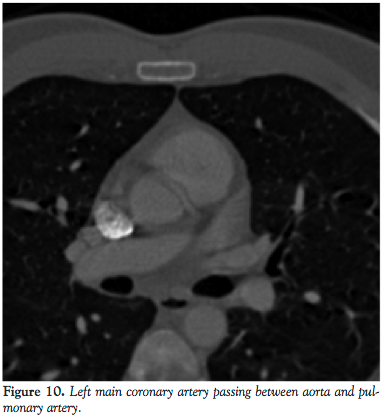

A subsequent CT angiography was obtained to delineate the course of this vessel. A 64-slice CT scan revealed that the left coronary artery coursed in between the aorta and pulmonary artery. In view of his ongoing chest pains, with a high risk of myocardial infarctions (MI), fatal arrhythmias, and sudden death, CABG was recommended.

The second case illustrates the left main coronary artery arising from the RCA and passing in between the aorta and main pulmonary trunk. This anatomy corresponds to the IIB2 classification of the isolated coronary artery anomalies.5 In this case, the risk of MI, fatal arrhythmias, syncope, and sudden death is significantly increased and it is postulated that this may occur as a result of an expansive effect of the aorta during exercise. This leads to the compression of the left coronary artery, which results in chest pains, angina, arrhythmias, and even sudden death. Our patient was found to have had a negative noninvasive work-up for coronary artery disease but in spite of this, had persistent recurrent chest pains for which coronary artery angiography was recommended.